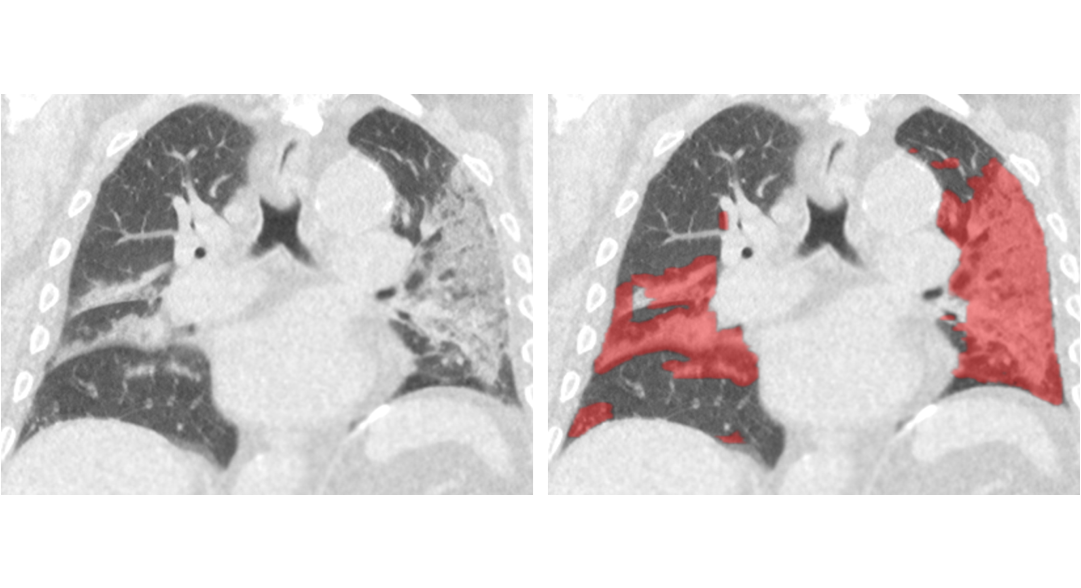

Thirona developed an AI algorithm that revolutionizes cystic fibrosis (CF) care.